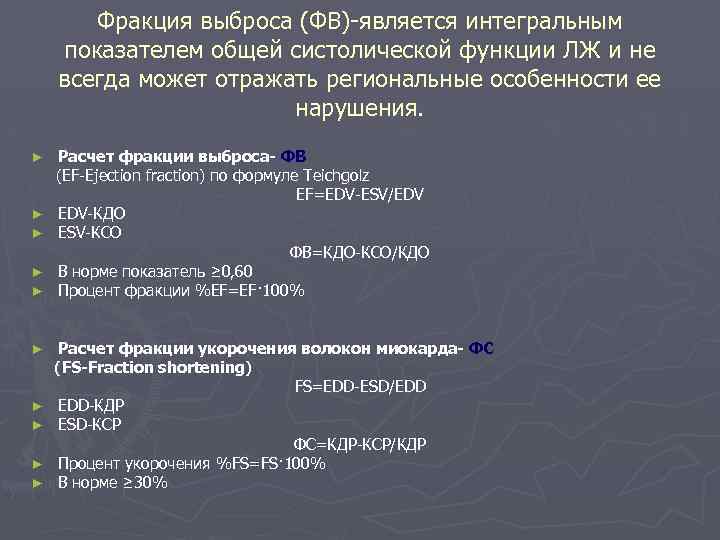

Фракция выброса (ФВ)-является интегральным показателем общей систолической функции ЛЖ и не всегда может отражать региональные особенности ее нарушения. ► ► ► ► ► Расчет фракции выброса- ФВ (EF-Ejection fraction) по формуле Teichgolz EF=EDV-ESV/EDV EDV-КДО ESV-КСО ФВ=КДО-КСО/КДО В норме показатель ≥ 0, 60 Процент фракции %EF=EF· 100% Расчет фракции укорочения волокон миокарда- ФС (FS-Fraction shortening) FS=EDD-ESD/EDD EDD-КДР ESD-КСР ФС=КДР-КСР/КДР Процент укорочения %FS=FS· 100% В норме ≥ 30%